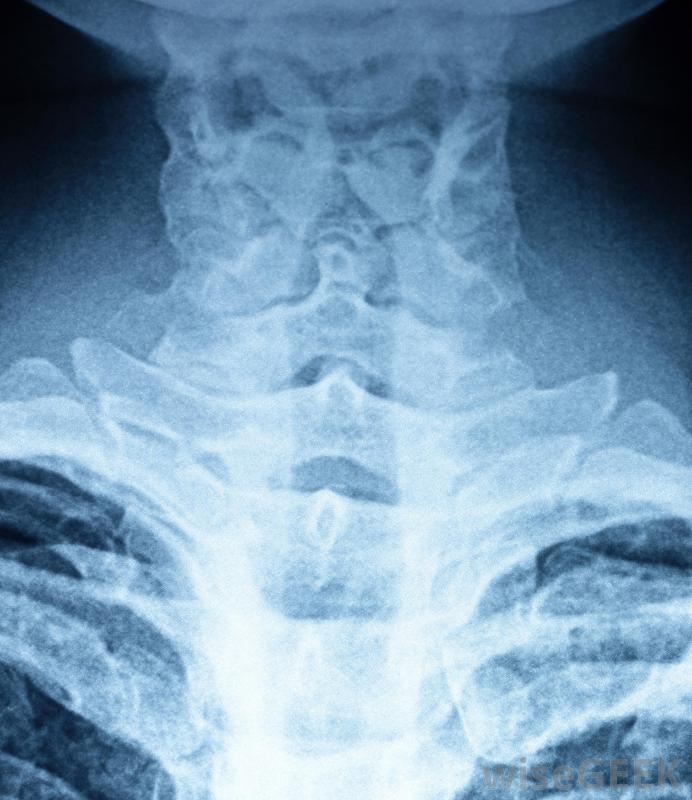

喉部CT扫描可生成颈部、头部和肩部的图像。有时也称为喉部扫描,喉部CT使用X射线来产生多个喉部内部的图像。这些图像从多个角度拍摄,作为一个整体进行编译和检查,以检查疾病和疾病的迹象。在测试过程中使用对比染料以获得尽可能完整的图像并不少见

喉咙的异常肿胀可能需要进行CT扫描。在进行喉部CT扫描时,病人被安置在一个可移动的检查床上,就像CT扫描仪一样,在测试之前,检查床会滑入隧道,在那里它保持原位,直到测试完成测试时,扫描器的X光设备会环绕患者的头部和颈部区域拍摄咽喉图像。每个角度都会拍摄一张快照图像。一旦所有目标区域都被X射线捕获,测试就完成了,图像被用来制作喉咙内部的三维图像

喉部CT扫描会产生喉咙内部的多张图像。